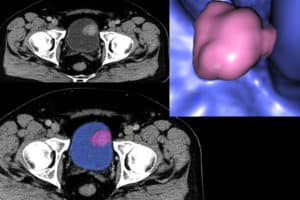

¿Qué debes saber del cáncer de vejiga?

De acuerdo a lo expuesto por Prevention.com el factor que juega en contra las mujeres, es que la mayoría, sino todas, las mujeres experimentamos una infección urinaria al menos una vez en la vida o más de una, haciendo que nos acostumbremos a esos síntomas que son, tremendamente parecidos a los del cáncer de vejiga. Entonces, asumimos, nos auto-diagnosticamos, compramos las cremas o remedios sin necesidad de receta sin saber que es probable que estemos frente a un cáncer mortal.